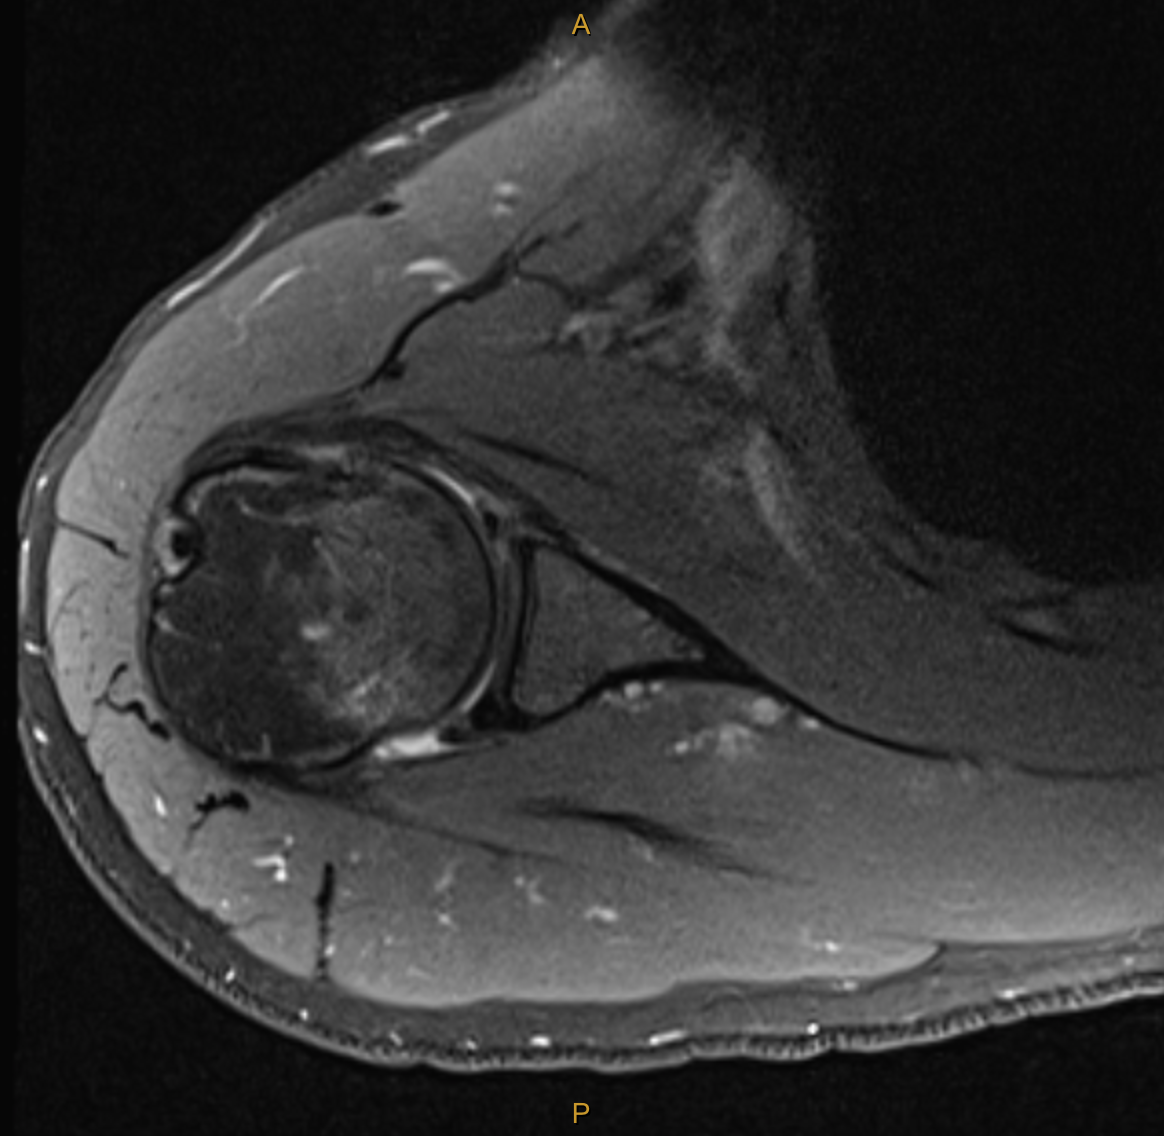

My clinical impression was the Ms C’s presentation was consistent with the event of an anterior dislocation and that MRI would best visualise the extent of tissue pathology. The report was incredibly detailed, and yet, there was additional structural damage which was not found until months later during surgery. The key findings (and my thoughts on their significance) are below:

Broad Hill-sachs lesion with underlying bone marrow oedema in keeping with recent anterior macroinstability event.

Impact fracture of the humeral head from contact on the glenoid. This fracture and indentation into the humeral head does not improve unless operated on and can lead to further instability and dislocation in positions of elevation and external rotation as the humeral head moves past the glenoid. This particular part of the injury is what is managed with the “remplissage” technique. (indication for surgery).

The bone marrow oedema can take between 3-6 months to settle (indication for wait and see).

Mild complex tear of the inferior to anterosuperior labrum extending from roughly the 6 o’clock position to the 10 o’clock position. [Fibrocartilaginous Bankart lesion]

No accompanying osseous Bankart lesion. [The glenoid was not fractured during dislocation]

There is slight elevation of the anterior glenolabral periosteum, consistent with some periosteal stripping.

No significant glenohumeral chondropathy.

Small joint effusion.

Intact cuff.

Not reported until surgery:Posterior labral tear and anteriorinferior chondral damage.

In addition to the exact MRI findings for this case, I have also added some images which outline the variants of a Bankart lesion and Hill-Sachs lesion below.